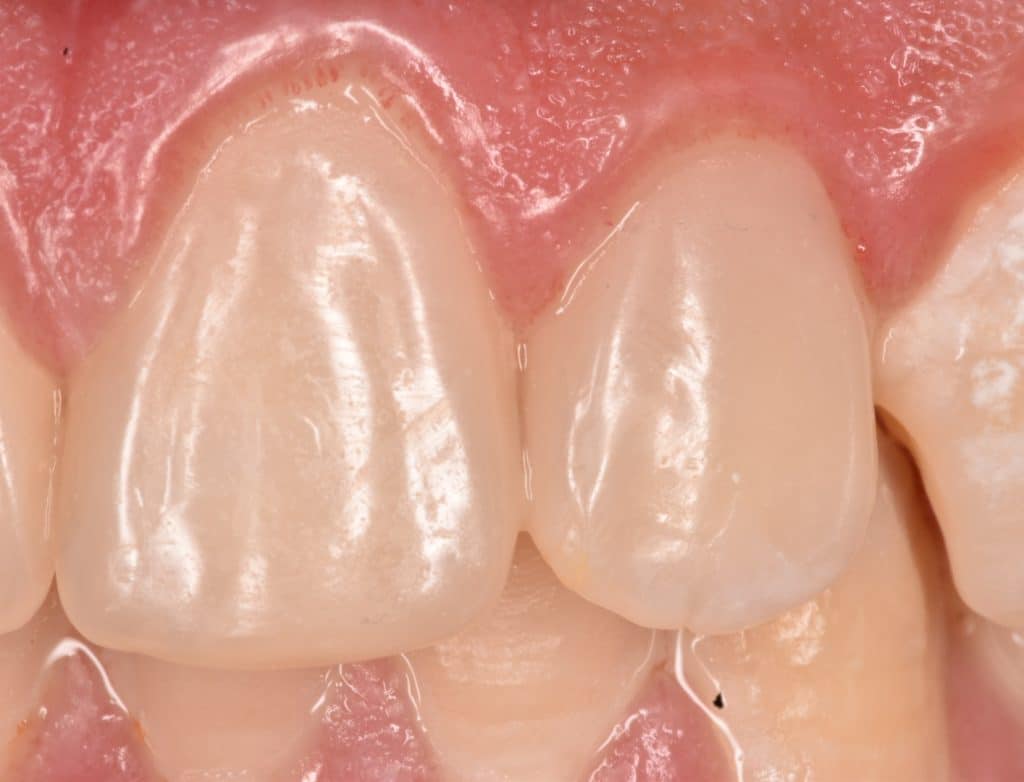

Immediate result

One month follow up

One month follow up, you can see the uniform color of the composite with the teeth 👍